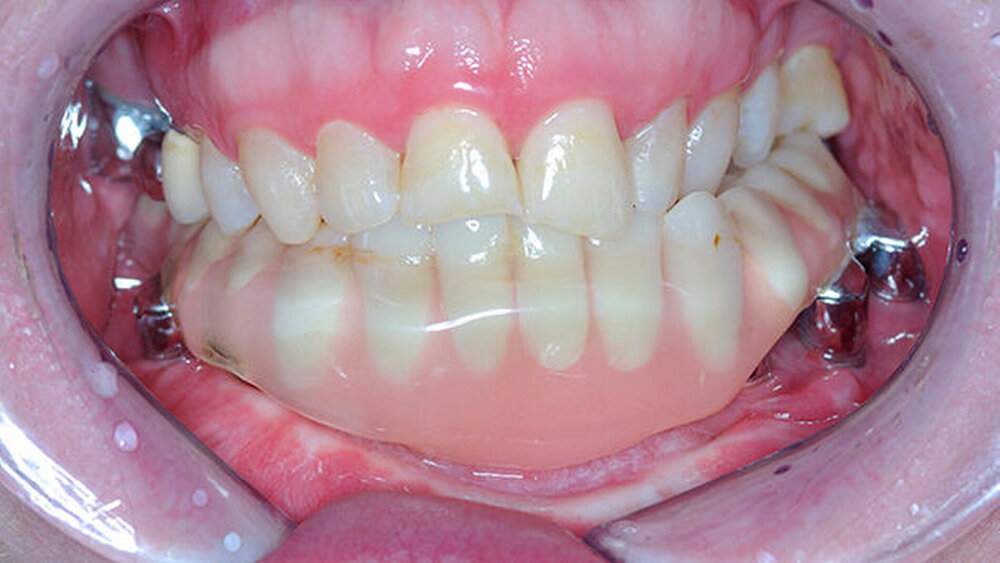

Das Verzeichnis bezieht sich in erster Linie auf Behandlungsorte, an denen intraorale defektprothetische Versorgungen durchgeführt werden. Falls auch extraorale Behandlungen durchgeführt werden, ist dies extra vermerkt. Für die Suche nach rein epithtetischen Behandlungsorten wird auf die Website desDeutschen Bundesverbandes der Epithetiker e.V.verwiesen.